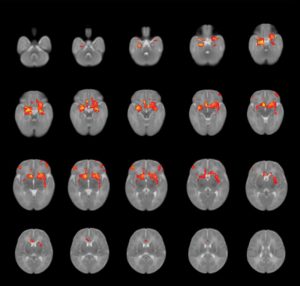

Para averiguarlo, los investigadores utilizaron imágenes de resonancia magnética para escanear los cerebros de 75 de los bebés 3 meses después del nacimiento. En un preprint publicado en octubre, encontraron que los bebés nacidos de personas que informaron más angustia prenatal (más síntomas de ansiedad o depresión) mostraron diferentes conexiones estructurales entre su amígdala, una región del cerebro involucrada en el procesamiento emocional, y su corteza prefrontal, un área responsable para las habilidades de funcionamiento ejecutivo [Manning, KY et al. Preprint at medRxiv https://doi.org/10.1101/2021.10.04.21264536 (2021)].

Escáneres cerebrales que muestran patrones de conectividad promedio entre la amígdala y otras regiones en bebés. El estrés relacionado con la pandemia durante el embarazo debilitó las conexiones en algunos bebés. Crédito: Kathryn Manning

En un pequeño estudio anterior, Lebel y su equipo establecieron el vínculo entre la depresión prenatal y las diferencias de conectividad cerebral en esas mismas áreas, y sugirieron que en los niños, estos cambios cerebrales se correlacionan con el comportamiento agresivo e hiperactivo en la edad preescolar de años [Hay, R. E. et al.J. Neurosci.40, 6969–6977 (2020)]. Otros equipos han encontrado que los cambios en la conectividad entre estas áreas en adultos son factores de riesgo para la depresión y la ansiedad [Holmes, AJ et al. J. Neurosci. 32 , 18087–18100 (2012)].“Esas son las áreas que están involucradas en el procesamiento de las emociones y muchos comportamientos diferentes”, dice Lebel.